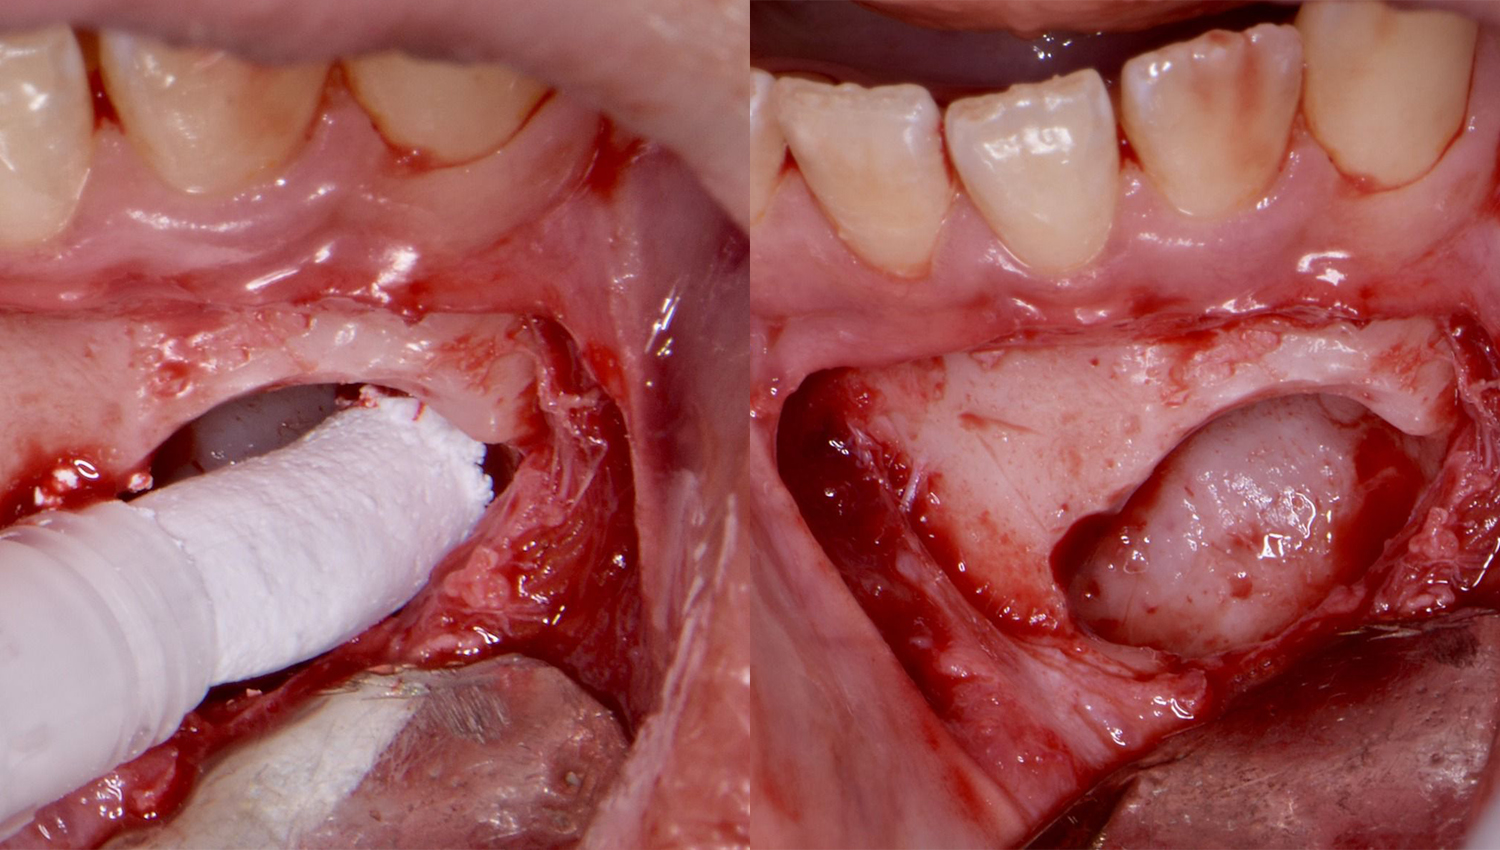

2. Removal of impacted tooth.

3. Usage of Powerbone Dental Putty for immediate grafting of the large 4-wall bone defect.